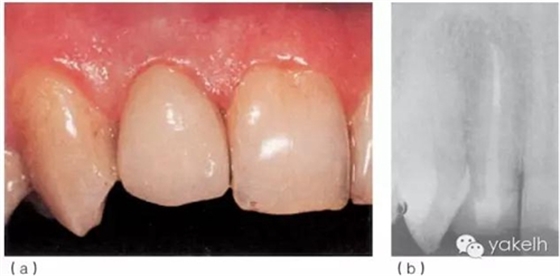

¤¤首先,使用超聲器械清理根管,確保樁道內(nèi)的根管壁上沒有牙膠及根管封閉劑殘留;通過試戴,選擇合適的纖維樁(圖6.3.5a);酒精擦拭樁道后,進(jìn)行酸蝕、沖洗、干燥;使用復(fù)合樹脂粘結(jié)劑粘樁(圖6.3.5b),光固化(圖6.3.5c);在樁及剩余牙體表面涂布牙本質(zhì)粘結(jié)劑,逐層堆塑樹脂核;樹脂核完成后,即刻行冠部預(yù)備(圖6.3.5d);制取印模,使用術(shù)前模型制作丙烯酸臨時冠;拍攝術(shù)后X線片(圖6.3.5e);2周后復(fù)診,粘固永久性全冠(圖6.3.6a);1年后復(fù)查,患者無不適,根尖X線片顯示患牙根尖周組織正常(圖6.3.6b)。

圖6.3.6(a)粘固永久性全冠。(b)12術(shù)后1年復(fù)查X線片。